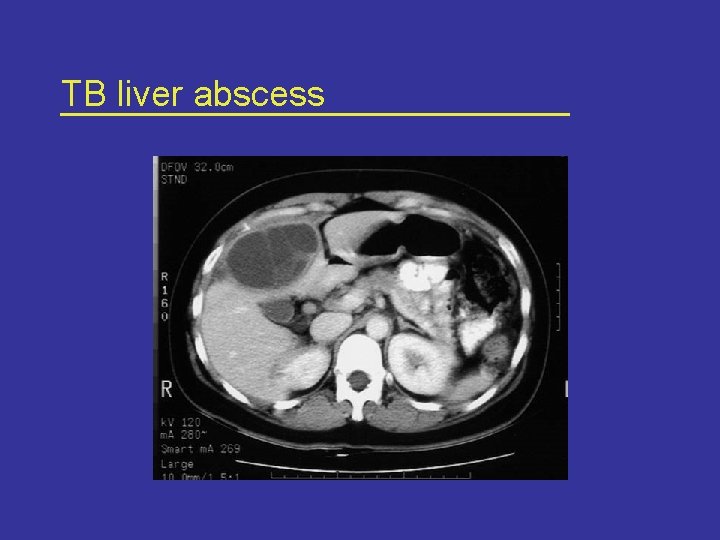

Diagnostic challenge • Pre-operative diagnosis often difficult • Other pathological lesions can mimic clinical and radiological characteristics*: – – – Simple cyst Hydatid cyst Liver abscess Cystic degeneration of liver neoplasm Caroli’s disease Polycystic liver disease *Lewis et al Arch Surg. 123, 563 -8, 1988.

Diagnosis and intervention • Final pathology of 15 patients with pre-op Dx of Biliary Cystadenoma – – – Biliary cystadenomcarcinoma Biliary cystadenoma HCC Liver cyst TB liver abscess Resolving liver abscess 1 6 1 5 1 1

TB liver abscess